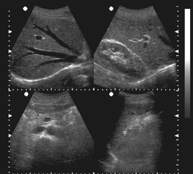

高清晰图像:

显示模式: B型、B/B型、4B型、B+M型、M型。